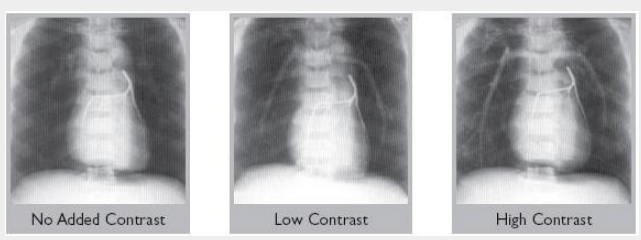

不同程度的血管對比可用

肺動脈注射血液當(dāng)量塑料。

提供血液當(dāng)量肺動脈,或添加低或高對比劑。